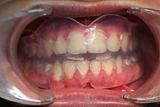

![]() |

| Unauffällig geklebte Drähte auf der Innenseite | Abnehmbare Geräte, Platten, häufig nur nachts getragen | Positioner. |